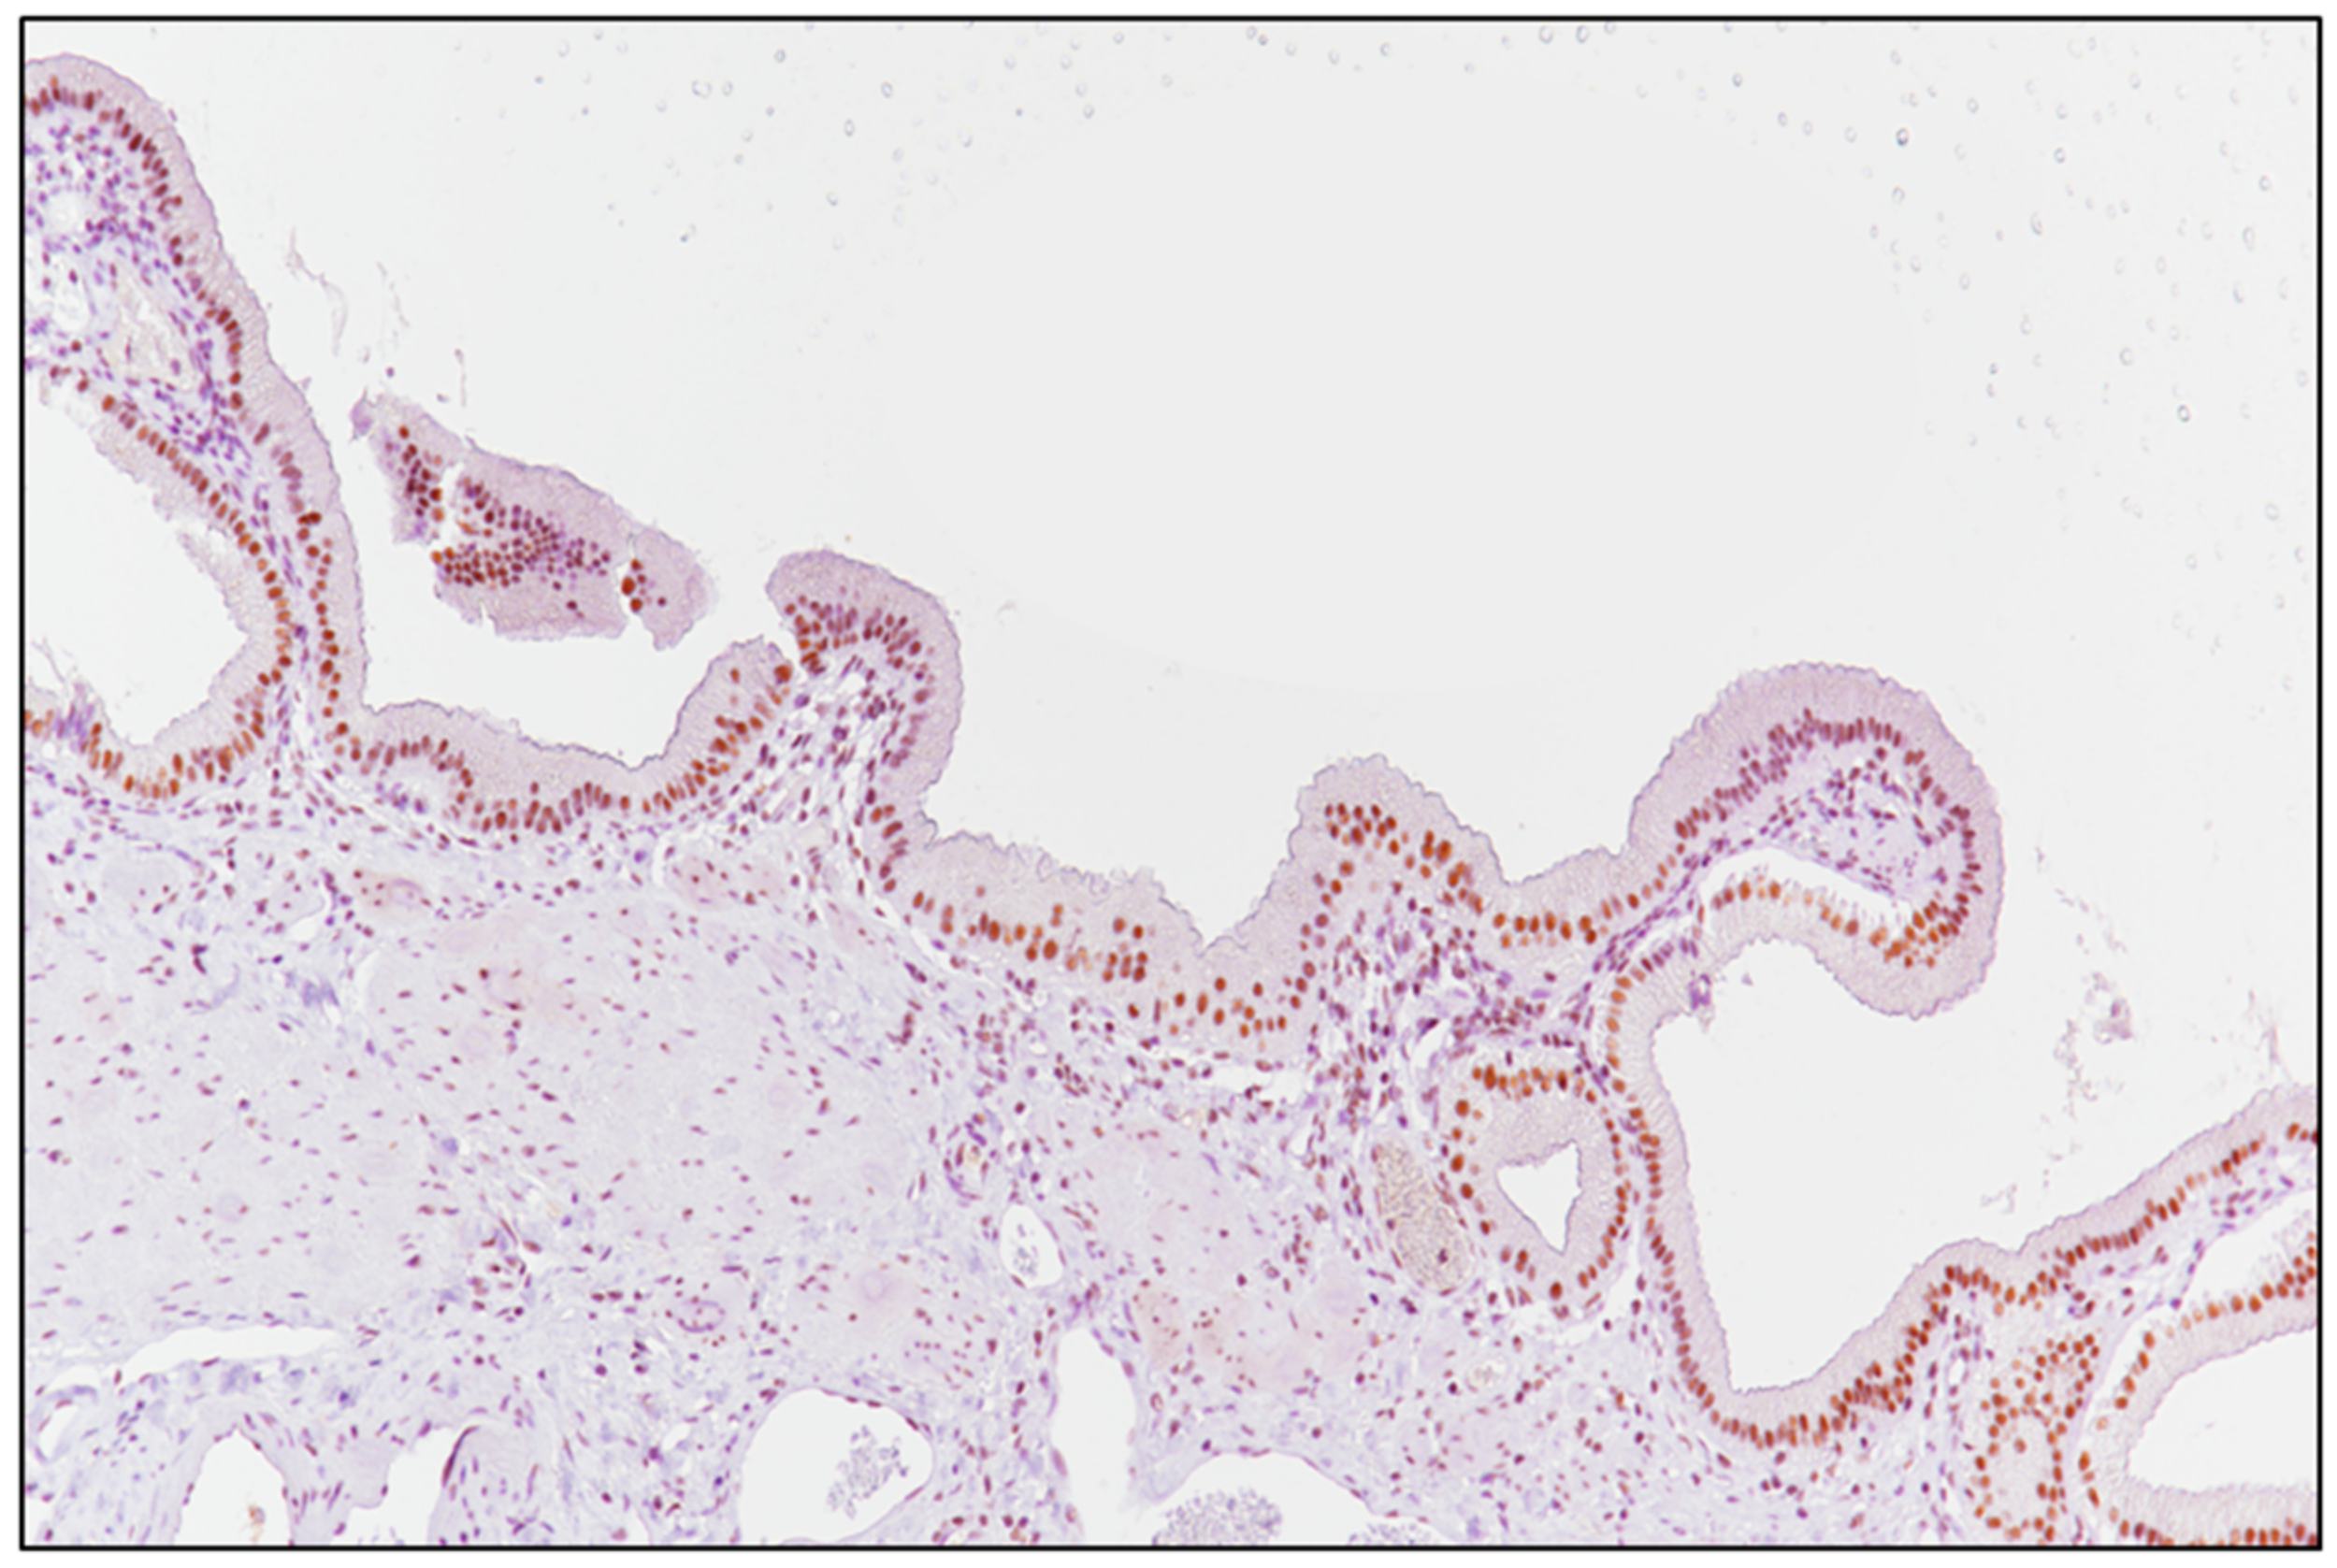

The detection of brown chromogen within tumor nuclei was considered as positive SRSF1 immunostaining; unaffected gallbladder tissue was adopted as a positive control (Figure 1), while negative control slides were obtained by incubating them with phosphate-buffered saline (PBS) instead of the primary antibody. A semi-quantitative analysis of the cases stained with SRSF1 was performed, as previously described [25,26,27]: briefly, the immunoreactivity score (IRS) was obtained by multiplying the intensity of staining (IS) and the percentage of positive cells (extent score; ES): if the IRS was ≤6, the SRSF1 expression was considered to be “low” (L-IRS), while an IRS > 6 was considered to be “high” expression (H-IRS).

Figure 1.

Unaffected gallbladder mucosa served as a positive control for SRSF1 (immunoperoxidase staining; original magnification 150×).